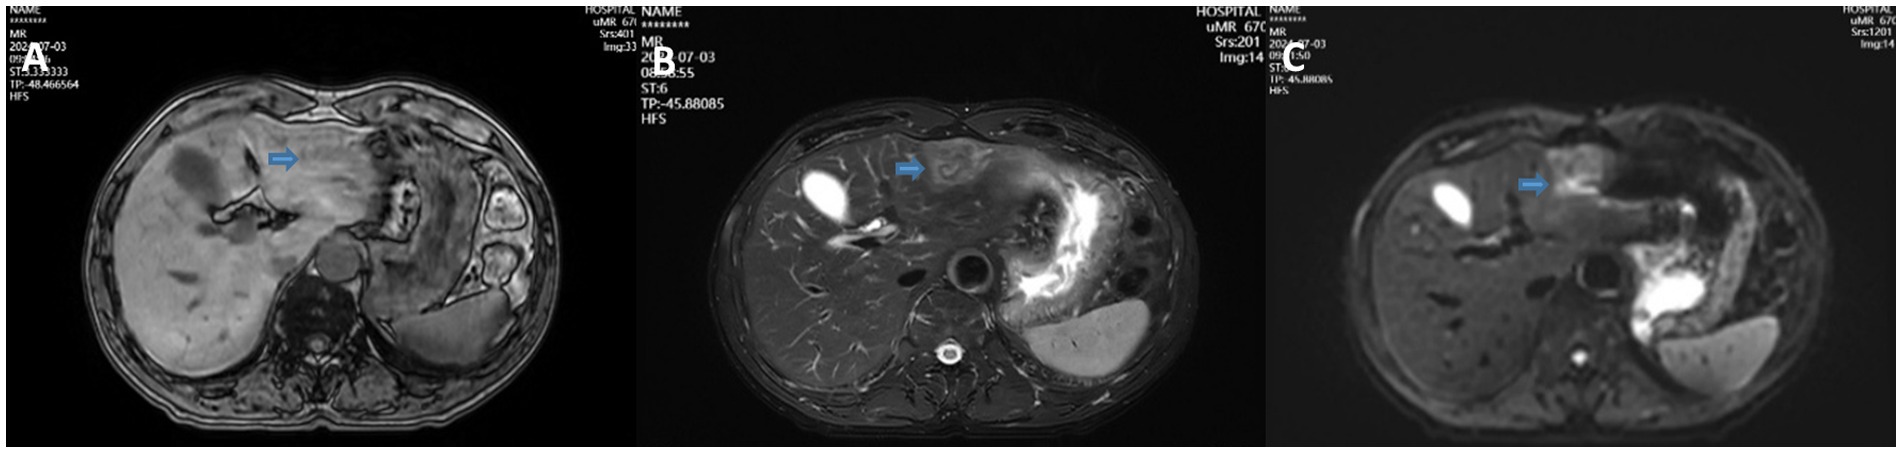

A 68-year-old male patient was diagnosed with nasopharyngeal squamous cell carcinoma (T3N2M0, EGFR positive, Ki-67 index 60%) on 20 December 2021, after presenting with headache and nasal congestion. He received concurrent chemoradiotherapy with the GP regimen (gemcitabine plus cisplatin) at the Affiliated Hospital of Chengde Medical College. Post-treatment evaluations performed every 6 months demonstrated no evidence of local recurrence or distant metastasis, and the patient remained clinically stable. On 14 July 2024—approximately 31 months after the initial diagnosis of NPC—routine follow-up CT revealed a solid low-density lesion (5 × 4 × 3 cm) in the left lateral lobe of the liver (T1 hypointense, T2 slightly hyperintense, markedly restricted diffusion on DWI), accompanied by multiple enlarged hilar lymph nodes. The imaging findings were highly suggestive of hepatic metastasis (Figure 1). Serum tumor markers CEA, AFP, and CA19-9 were all within normal ranges. After referral to Peking Union Medical College Hospital, repeat CT/MRI confirmed similar findings and raised suspicion of intrahepatic cholangiocarcinoma. A preoperative liver biopsy was recommended by the multidisciplinary team to clarify the nature of the lesion; however, the patient declined due to financial constraints and personal preference, citing concerns about procedural risk and potential treatment delay. Other diagnostic modalities, such as PET-CT, inflammatory marker testing (CRP, ESR), and gadoxetic acid-enhanced MRI (EOB-MRI), were also not performed for similar economic and logistic reasons. Given the available radiologic and clinical evidence, surgical resection was performed for both diagnostic and therapeutic purposes. The patient underwent laparoscopic left lateral lobectomy and hilar lymph node dissection at the Affiliated Hospital of Chengde Medical College. Intraoperatively, nodular enlargement of the hilar lymph nodes was noted. Gross examination revealed a 14 × 9 × 5 cm specimen of hepatic tissue containing a 5 × 4 × 3 cm nodular mass, along with a 1.5 cm nodular hilar lymph node. Postoperative histopathology demonstrated dense infiltration of neutrophils, lymphocytes, and eosinophils, with focal necrosis and granulation tissue proliferation but no malignant cells, consistent with an inflammatory pseudotumor (Figure 2). The diagnosis was confirmed through histopathological consultation at Peking Union Medical College Hospital. The patient received 2 weeks of postoperative anti-infective therapy, recovered uneventfully, and showed no recurrence at one-year follow-up.

Figure 1. T1WI (A), T2WI (B), and DWI (C) showing a solid low-density mass in the left lateral lobe of the liver.